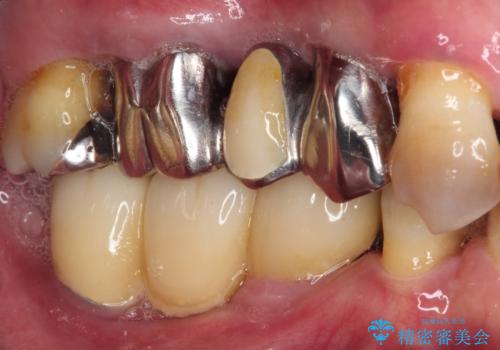

強い咬合力で奥歯がボロボロに インプラント治療による咬合回復と全顎セラミック治療

- 奥歯が咬みにくく、前歯がぐらぐらするとのことで来院された患者様です。

咬合力が強く、奥歯が欠損している状態でした。

欠損部はインプラントによる補綴治療を行うこととし、臼歯部が安定した後に、上下前歯部をオールセラミッククラウンにて補綴治療を行うこととしました。